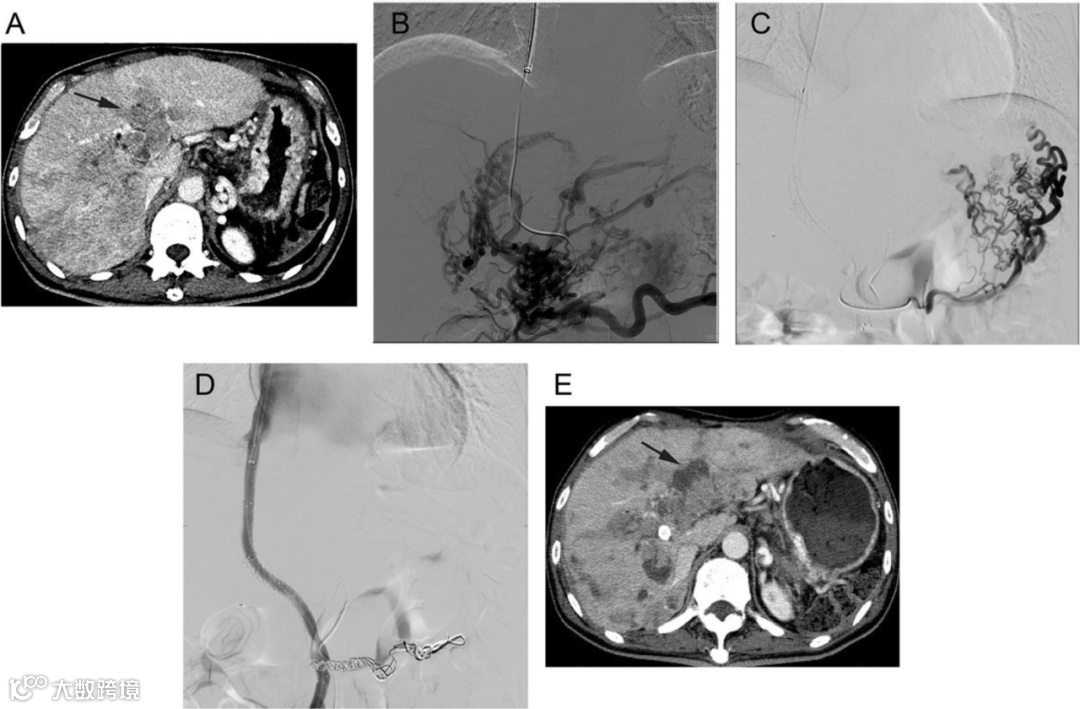

Qiu Z, Wang G, Yan H, et al. TIPS plus sequential systemic therapy of advanced HCC patients with tumour thrombus-related symptomatic portal hypertension. Eur Radiol. 2022.

简评丨孙军辉

PVTT可阻断门静脉血流而加重门静脉高压,导致症状性门静脉高压(SPH)并发症,比如消化道出血或顽固性胸腹水,进而会限制靶向药物、免疫药物等系统性抗肿瘤药物的应用,因此,评估门静脉高压的临床症状对促进抗肿瘤治疗方案的发展至关重要;TIPS是降低肝硬化患者门静脉高压并发症的有效治疗方法,既往研究已经显示TIPS对于HCC伴SPH的治疗是可行的。